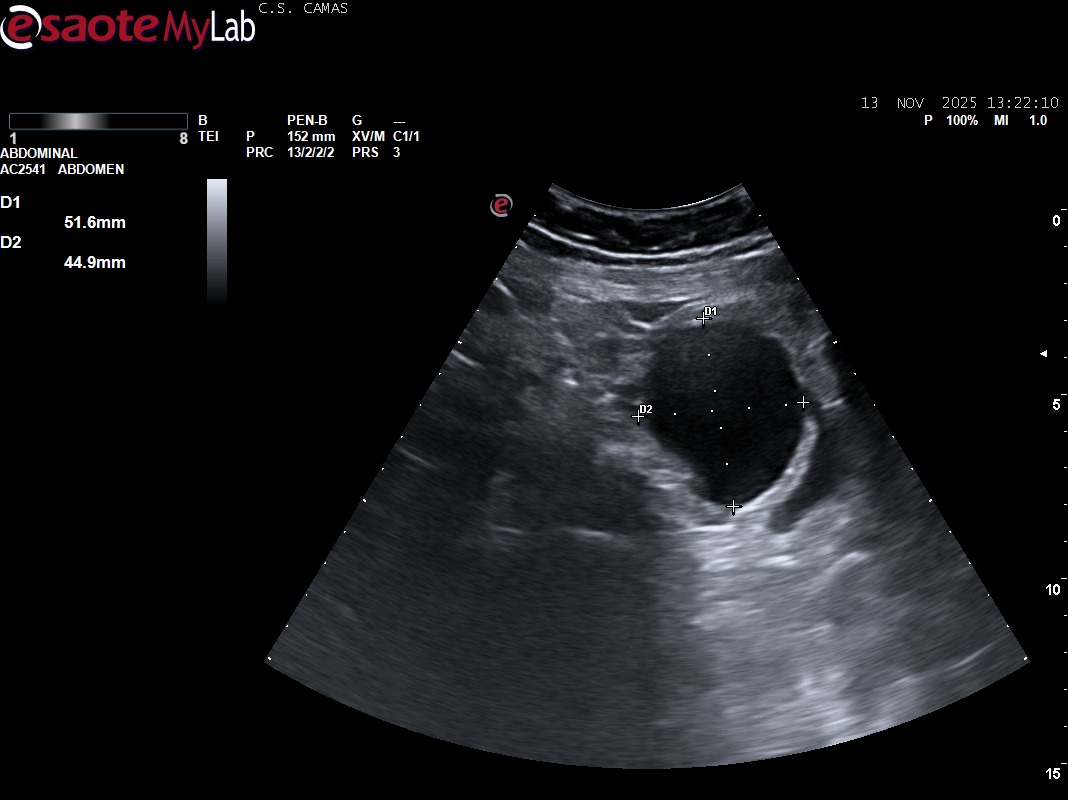

Hallazgos ecográficos

Ecografía clínica (POCUS):

Dolor lumbar irradiado secundario a masa anexial derecha compatible con quiste ovárico de gran tamaño y compresión vesical.

Es importante diferenciar quistes ováricos simples sin ecos internos, como en este caso, de aquellos con ecos en su interior, característicos de quistes hemorrágicos.